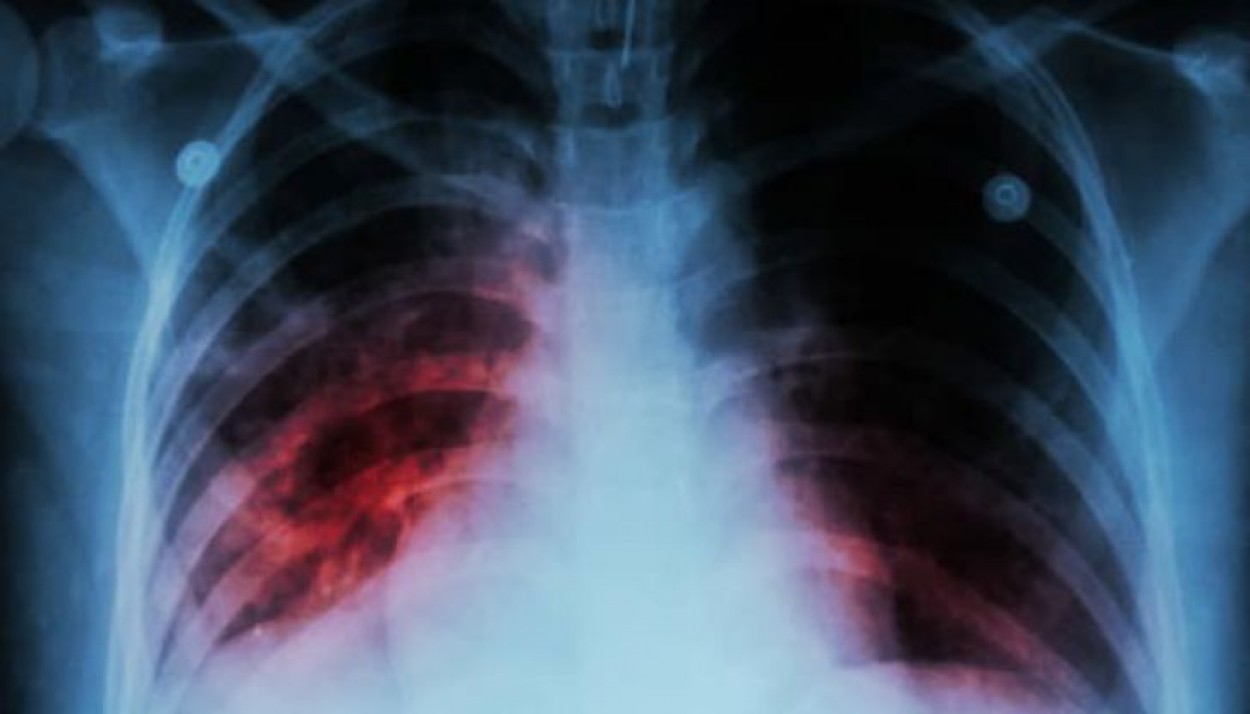

Tuberkuliozę sukelia bakterijos. Dažniausiai šios bakterijos atakuoja plaučius, tačiau taip pat gali paveikti inkstus, stuburą ar net smegenis.

Tuberkuliozė yra labai pavojinga infekcinė liga, nors daugelis sergančiųjų serga latentine šios ligos forma, tačiau apie 10 procentų visų sergančiųjų ši infekciją progresuoja į aktyvią tuberkuliozę, kuri negydoma gali pražudyti žmogų. Kvėpavimo organų tuberkuliozę sukelia bakterija, kuri plinta per orą. Pagrindinis šių bakterijų šaltinis yra žmogus sergantis atvira plaučių tuberkulioze. Didžiausią riziką užsikrėsti tuberkulioze, turi artimai ir ilgą laiką bendraujantys su atvira tuberkulioze sergančiais asmenimis asmenys.